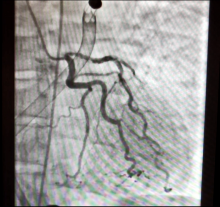

A 37-year-old woman presented with altered mental status and profound hypoxia. She had a history of PEs and end-stage renal disease on hemodialysis. Computed tomography angiogram demonstrated organized lining thrombi, causing vascular obstruction in branches of both pulmonary arteries. Significant thrombus was also demonstrated in the right atrium and superior vena cava. Transesophageal echocardiography revealed a significantly dilated right ventricle and severe tricuspid regurgitation. An Impella RP® (Abiomed, Danvers, MA, USA) device was placed for severe right ventricular failure. Thrombolysis was attempted but it failed. Weaning from Impella support was also unsuccessful, and a decision to perform a pulmonary thromboendarterectomy was made.

The right pulmonary artery was approached, medial to the superior vena cava. After the patient was cooled to 20°C, the aorta was cross-clamped and a single dose of Custodiol-HTK cardioplegic solution was administered. An incision was made in the right pulmonary artery and carried past the take-off of the middle lobe artery. Circulatory arrest was then initiated. An olive tip suction instrument was used to develop a thromboendarterectomy plane. The thromboendarterectomy extended into the subsegmental vessels. Once the right-sided thromboendarterectomy was completed, circulation was restarted and the arteriotomy was repaired using a pericardial patch with a continuous 6-0 polypropylene suture. The total circulatory arrest time was 15 minutes.

Circulatory arrest was reinitiated after 20 minutes of reperfusion. The left pulmonary artery was incised beginning at the midpoint of the pulmonary trunk. The Impella device was retracted away from the left pulmonary artery. A thromboendarterectomy of the segmental and subsegmental branches was done. After the left-sided thromboendarterectomy was completed, the Impella device was reinserted and the arteriotomy was closed. Circulation was restarted. The total circulatory arrest time was 15 minutes.